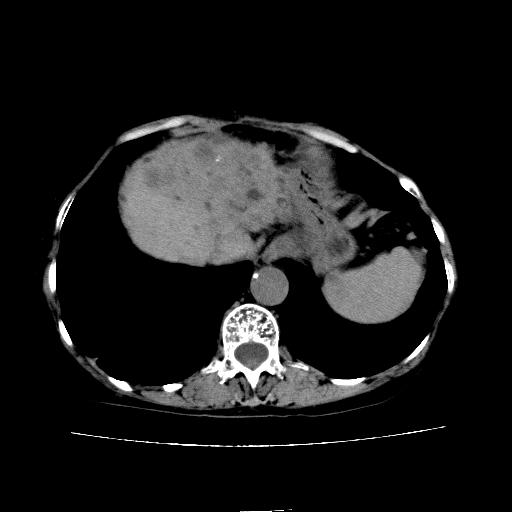

静脉期

看片子胆管里结石,肝上显示的占位会不会是胆管癌?大家帮忙看看,图像不太好,手头的处理文件没有,大致转换了一下,有原始图像数据

考虑胆管结石伴左肝内胆管扩张,不除外胆管细胞癌。

1)考虑肝左叶胆管细胞癌并肝内转移。2)肝左叶肝内胆管结石。